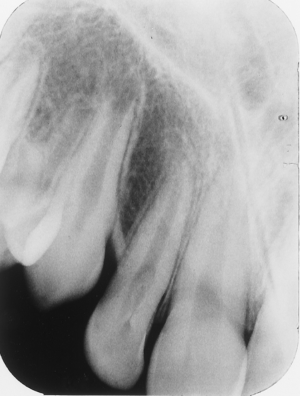

List the anomalies seen in this radiograph of the 3rd molar region.

Impacted 2nd molar and microdontic 3rd molar

Impacted 3rd molar and supernumerary 4th molar

Impacted 2nd molar; microdontic, impacted 3rd molar; and dilacerated mesial root of the 2nd molar

Impacted 3rd molar; impacted, supernumerary 4th molar; and dilacerated mesial root of the 2nd molar